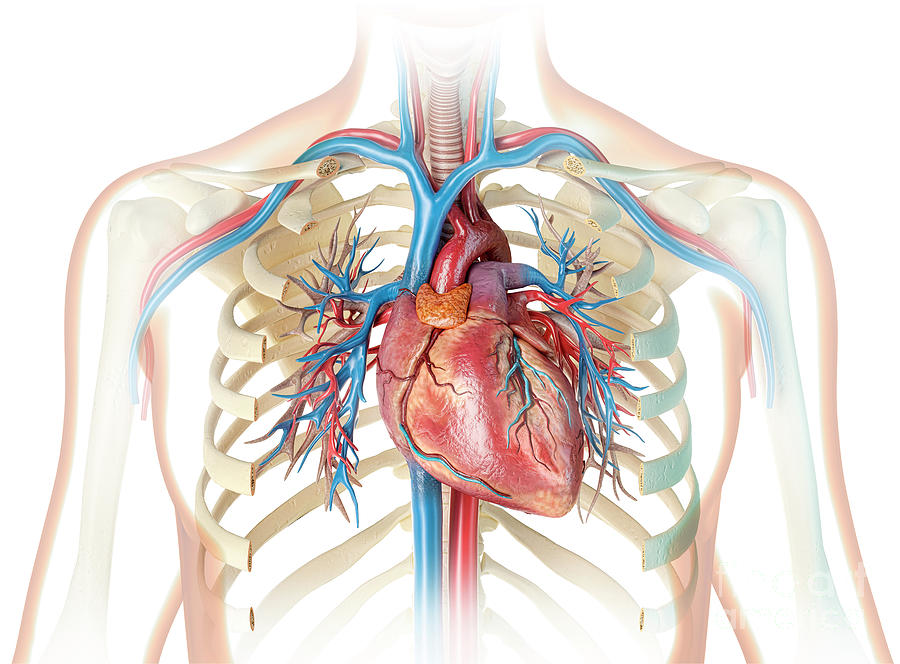

Изображения и визуализация внутренних органов человека